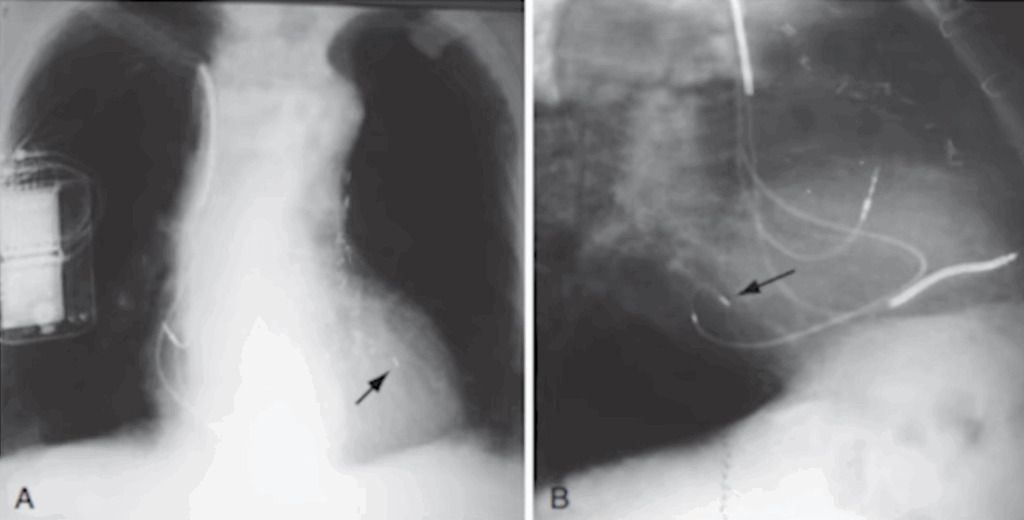

This case highlights the importance of using both LAO and RAO views.

If you rely only on the LAO view, you may miss crucial information—such as the presence of a stenosis—that becomes obvious only when combining both projections.

Keep in mind that if you’re struggling to cannulate a branch, sub-selection catheters are available to help navigate tortuous anatomy. And always remember: never force the lead or the catheter.

Here’s what happens when you apply force with a steep angulation: you can create a dissection, and in that situation you must immediately check the pericardium, as it can progress to a cardiac tamponade.

Never apply force when you feel resistance. If the lead or wire gets stuck, use a sub-selection catheter, which is more flexible and helps you navigate around tortuous segments safely.